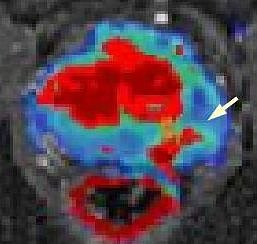

MRT von Prostata (Foto: SHK)

Bei diesem Jahrestreffen der nordamerikanische Röntgengesellschaft, an dem 65.000 Fachleute teilnehmen, wird der Nordhäuser Mediziner über die MR-gestützte Abklärung von auffälligen Befunden an der Prostata referieren. Das Nordhäuser Krankenhaus ist eines von sehr wenigen Häusern in Deutschland und bislang das einzige in Thüringen, das diese interventionelle Methode anbietet (siehe Foto, Pfleil zeigt auf Karzinom). In diesem Zusammenhang besteht seit längerem eine enge Zusammenarbeit mit dem Fraunhofer-Institut in Bremen.